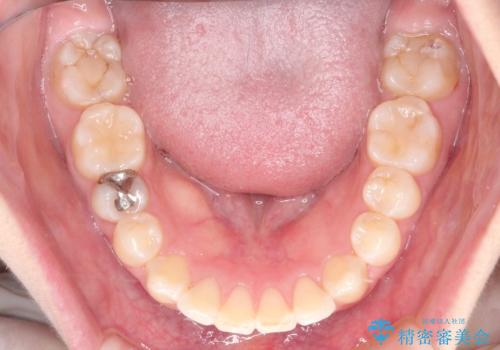

見た目だけではなくかみ合わせも良くなったと満足して頂きました。

治療後は見た目だけでなく、噛みやすくなったと満足していただけました。